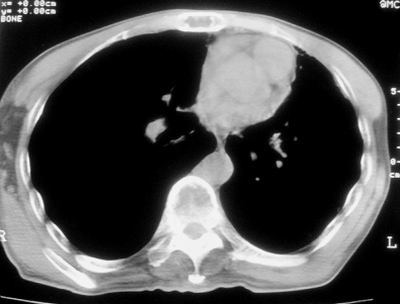

标题: CT11864:男,47岁,反复咳嗽、咯痰、咯血3年,请分析. [打印本页]

患者,男,47岁,反复咳嗽、咯痰、咯血3年,再发5天。痰培养未找到真菌、抗酸杆菌、癌细胞。

左肺上叶体积明显缩小,其内见多发透光区,纵隔向左侧移位,左肺下叶多发班片状病灶,边界模糊,1左肺上叶先天肺发育不全,2左肺下叶肺炎,

左肺上叶结核伴肺纤维化,纵隔移位,左肺下叶感染性病变,建议抗炎抗结核后复查,双肺气肿.

以下是引用xulianj在2008-2-25 21:01:00的发言:[br]左肺上叶结核伴肺纤维化有霉菌球形成,纵隔移位,左肺下叶感染性病变,建议抗炎抗结核后复查,双肺气肿.

考虑:左肺慢纤伴霉菌球形成、双肺全小叶型肺气肿。

1)考虑为:左肺上叶肺结核(空洞形成),伴左下肺感染;不排除霉菌感染可能。2)肺气肿。

左肺上叶结核伴肺纤维化空洞形成并左肺下叶感染,纵隔牵拉移位,建议作进一步检查排除左侧肺霉菌感染可能。